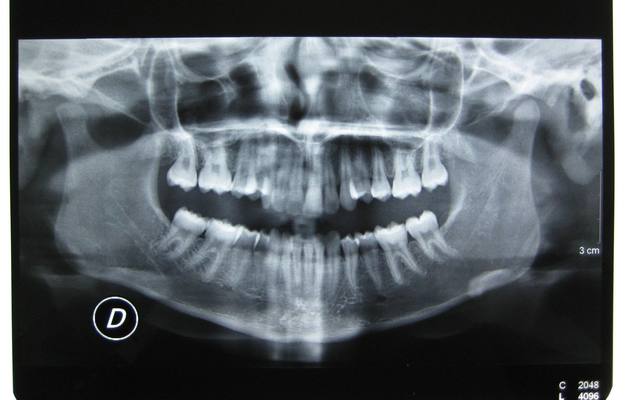

J'ai une patiente de 14 ans qui présente une full classe II due à un maxillaire en proposition car sur une base du crâne trop longue en antérieur. Le maxillaire a une longueur normale.

Voici les photos, radios et moulages du cas

Le maxillaire n'est pas si avancé que cela, par rapport a mac namara ( mais c'est normale, si c'est la base du crane qui est augmenté ) : donc : chirurgie pour raccourcir la base du crane ?

Sinon, extraction 14 24, c'est quand même moins lourd qu'un Lefort.